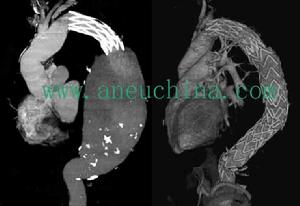

胸降主動脈動脈瘤如動脈瘤病變比較局限,阻斷主動脈血流的時間在30分鐘以內,則僅需套用體表降溫以增強脊髓的缺血缺氧耐受力,並於術中套用靜脈滴注硝普鈉控制上半身高血壓,無需套用外分流或左心轉流等方法。進入胸腔後先局部游離動脈瘤近、遠側主動脈。大多數病例動脈瘤近端在左鎖骨動脈下方,僅需在主動脈弓遠段放置阻斷鉗。如動脈瘤近端緊靠左鎖骨下動脈開口,則需在左頸總動脈與左鎖骨下動脈之間鉗夾主動脈弓,同時鉗夾左鎖骨下動脈。然後於動脈瘤遠側放置降主動脈阻斷鉗。阻斷血流後,縱向切開動脈瘤。縫扎主動脈後壁肋間動脈開口。但對於長段降主動脈動脈瘤應注意儘可能保留數支肋間動脈。為此可斜向切斷降主動脈的一端,保留肋間動脈開口部位的主動脈後壁,然後用一段口徑比主動脈略小、長度適當並經過預凝處理的人造血管分別與主動脈近、遠段切端作不漏血對端吻合術。吻合術完成後,先放鬆遠段主動脈阻斷鉗,排盡人造血管記憶體留的氣體,並觀察吻合口無漏血後,緩慢地取除主動脈遠段和近段阻斷鉗,用動脈瘤壁包繞裹緊人造血管縫合切緣。